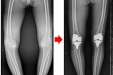

守护膝关节健康,且行且珍“膝”——严重膝关节病变,膝关节置换能帮到您!